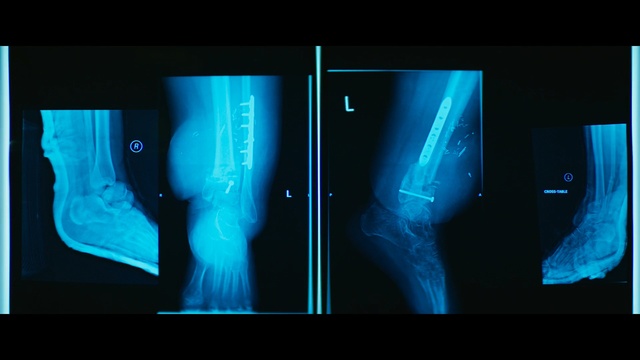

Best Video References: Rentgen